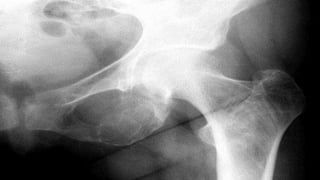

 x-ray the hand for signs of bone resorption.

INVESTIGATIONS  High serumCalcium sometimes you may find it low, so you have to repeat it again.  High PTH  Low serum Phosphate  High Chloride  x-ray the hand for signs of bone resorption.